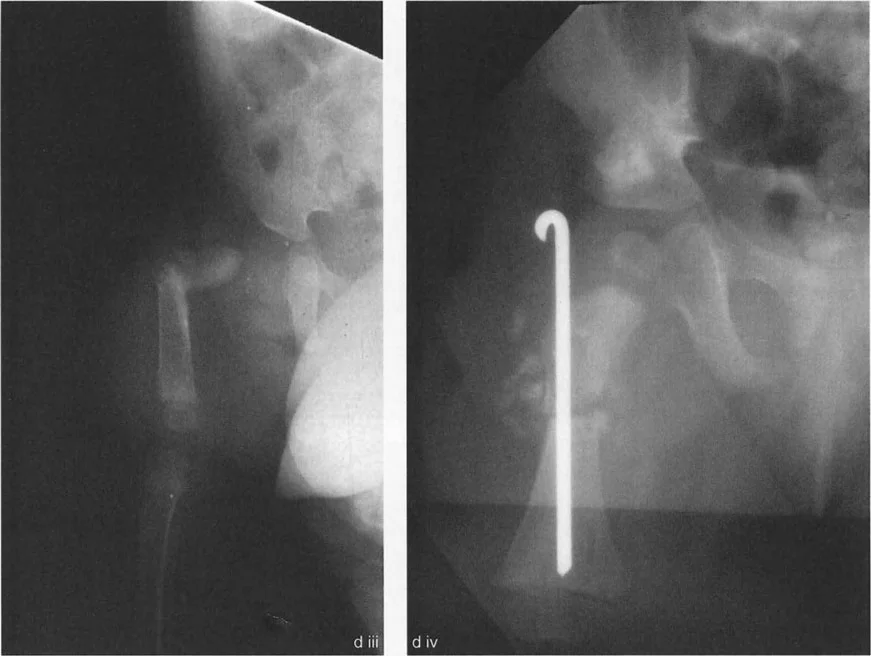

جراحة عظم الفخذ الفحجاء (Valgus Osteotomy) لتصحيح الورك الفحجاء (Varus Deformity)

تُجرى هذه الجراحة عندما يكون عنق الفخذ مائلاً جدًا للأسفل (الورك الفحجاء). تهدف العملية إلى زيادة زاوية عنق الفخذ، مما يجعلها أكثر عمودية.

• التقنية: تتطلب الجراحة قدرة كافية على تقريب رأس الفخذ. في بعض الحالات، قد يكون هناك تقلص في عضلات التبعيد (مثل العضلة الموترة للفافة اللاتسية والعضلة الألوية الوسطى والصغرى)، مما يحد من التقريب.

• بضع وتر المقربة (Adductor Tenotomy): قد يكون ضروريًا بعد جراحة عظم الفخذ الفحجاء، خاصة بسبب تأثير إطالة الساق الناتج عن هذه الجراحة.

• إطالة آلية المبعدة: في حالات الورك الفحجاء الخلقي، قد تتطلب إطالة آلية العضلة المبعدة. الأستاذ الدكتور محمد هطيف، في عام 1998، طور إجراءً جديدًا يتضمن إزالة كامل ارتباط العضلة الألوية الوسطى والصغرى بالتواصل مع العضلة رباعية الرؤوس (العضلة المتسعة الوحشية). هذا الإجراء يحرر المدور الكبير من تقلص التبعيد خارج المفصل، مما يسمح بتقريب عظم الفخذ القريب ضمن قيود الارتباطات الكبسولية. كما يتطلب تحرير العضلة الكمثرية التي يمكن أن تحد من الدوران الداخلي والمد والتقريب. يتم إعادة تثبيت الوتر المشترك لهذه الوحدة إلى المدور الكبير بعد تقريب الورك لتصحيح تشوه الورك الفحجاء.

• القيود داخل المفصل: إذا كان تحديد التقريب ناتجًا عن تقلص كبسولي أو التصاقات داخل المفصل، فقد يتطلب الأمر بضع كبسولة (Capsulotomy) لتحقيق التصحيح الكامل. إذا كان السطح المفصلي مشوهًا، فقد لا يمكن تحقيق التصحيح الكامل إلا بعد إعادة تشكيل رأس الفخذ.

جراحة عظم الفخذ الروحاء (Varus Osteotomy) لتصحيح الورك الروحاء (Valgus Deformity)

تُجرى هذه الجراحة عندما يكون عنق الفخذ مائلاً جدًا للأعلى (الورك الروحاء). تهدف العملية إلى تقليل زاوية عنق الفخذ، مما يجعلها أكثر أفقية.

• التقنية: تتطلب الجراحة قدرة كافية على تبعيد رأس الفخذ. عادةً ما لا تحد عضلات المقربة من تبعيد الجزء القريب من الفخذ بعد قطع العظم لأنها ترتبط بعيدًا عن مستوى قطع العظم.

• تأثير التقصير: تؤدي جراحة عظم الفخذ الروحاء إلى تقصير في طول الساق، مما يريح عضلات المقربة ويقلل الحاجة إلى بضع وتر المقربة.

• القيود داخل المفصل: إذا كان تحديد التبعيد ناتجًا عن عوامل داخل المفصل، فقد يتطلب الأمر بضع كبسولة وتحرير داخل المفصل. إذا كان السطح المفصلي مشوهًا، فقد لا يمكن تحقيق التصحيح الكامل إلا بعد إعادة تشكيل رأس الفخذ.